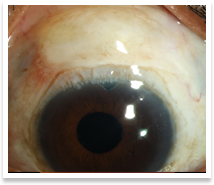

Glaucoma refers to progressive damage of the optic nerve(the nerve that carries visual information to the brain) secondary to numerous causes, the most well known of which are raised intraocular pressure(IOP, the pressure inside the eye) and vascular(blood supply related) disturbances. The essential feature of this condition is excavation of Optic Disc(the white portion of the disc) along with loss of the neuroretinal rim(the pink portion of the disc) Glaucoma affects the peripheral vision first (our perception of things in and around our point of interest or fixation point when we look at something) and the central vision later. Hence, it might be very difficult to pick up glaucoma until the damage is advanced. There are two major types of glaucoma : |